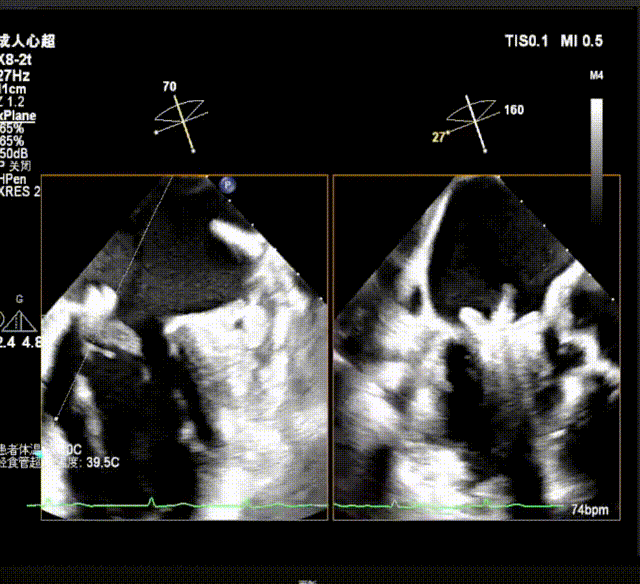

术中及术后即刻超声评估

测量穿刺点距离二尖瓣环的位置,测量为4.35cm;沿着导丝置入可调弯导引导管,使其穿出穿刺点2cm左右

经导管瓣膜夹输送系统进入左房,进行打弯调整使瓣膜夹朝向二尖瓣

瓣上M/L和A/P调整瓣膜夹,在X-plane进行超声确认(视频),进行弹道路径检查;

3D指示下调整瓣膜夹朝向病变区域

关闭瓣膜夹在超声指引下推进到左心室;打开瓣膜夹至120°,超声下抓捕瓣叶。

确定瓣膜夹与病变区域垂直后,放下夹片;超声确认前叶后叶都夹合充分,3D检查瓣膜夹位置.

瓣膜夹释放前评估发现返流改善明显,但是P1脱垂外侧仍有少量返流,综合考虑决定再植入一枚长宽瓣膜夹;

超声测量前瓣夹持长度0.91cm,后瓣夹持长度约1.14cm

第二枚瓣膜夹紧挨着第一枚瓣膜夹;夹合P2偏P1区脱垂,分担张力,稳定释放瓣膜夹,返流消失。

释放后平均压差2mmHg,瓣口面积可,超声PW显示左肺静脉收缩期逆流消失.

最终释放用多普勒超声评估返流程度,返流情况改善明显,术后仅残留少量反流( MR 1+),术后跨瓣压差5mmHg,无瓣口狭窄;肺静脉逆流情况消失,血流动力学显著改善;3D超声下,瓣膜组织桥稳定。术后即刻评估,返流几乎消失,手术成功。